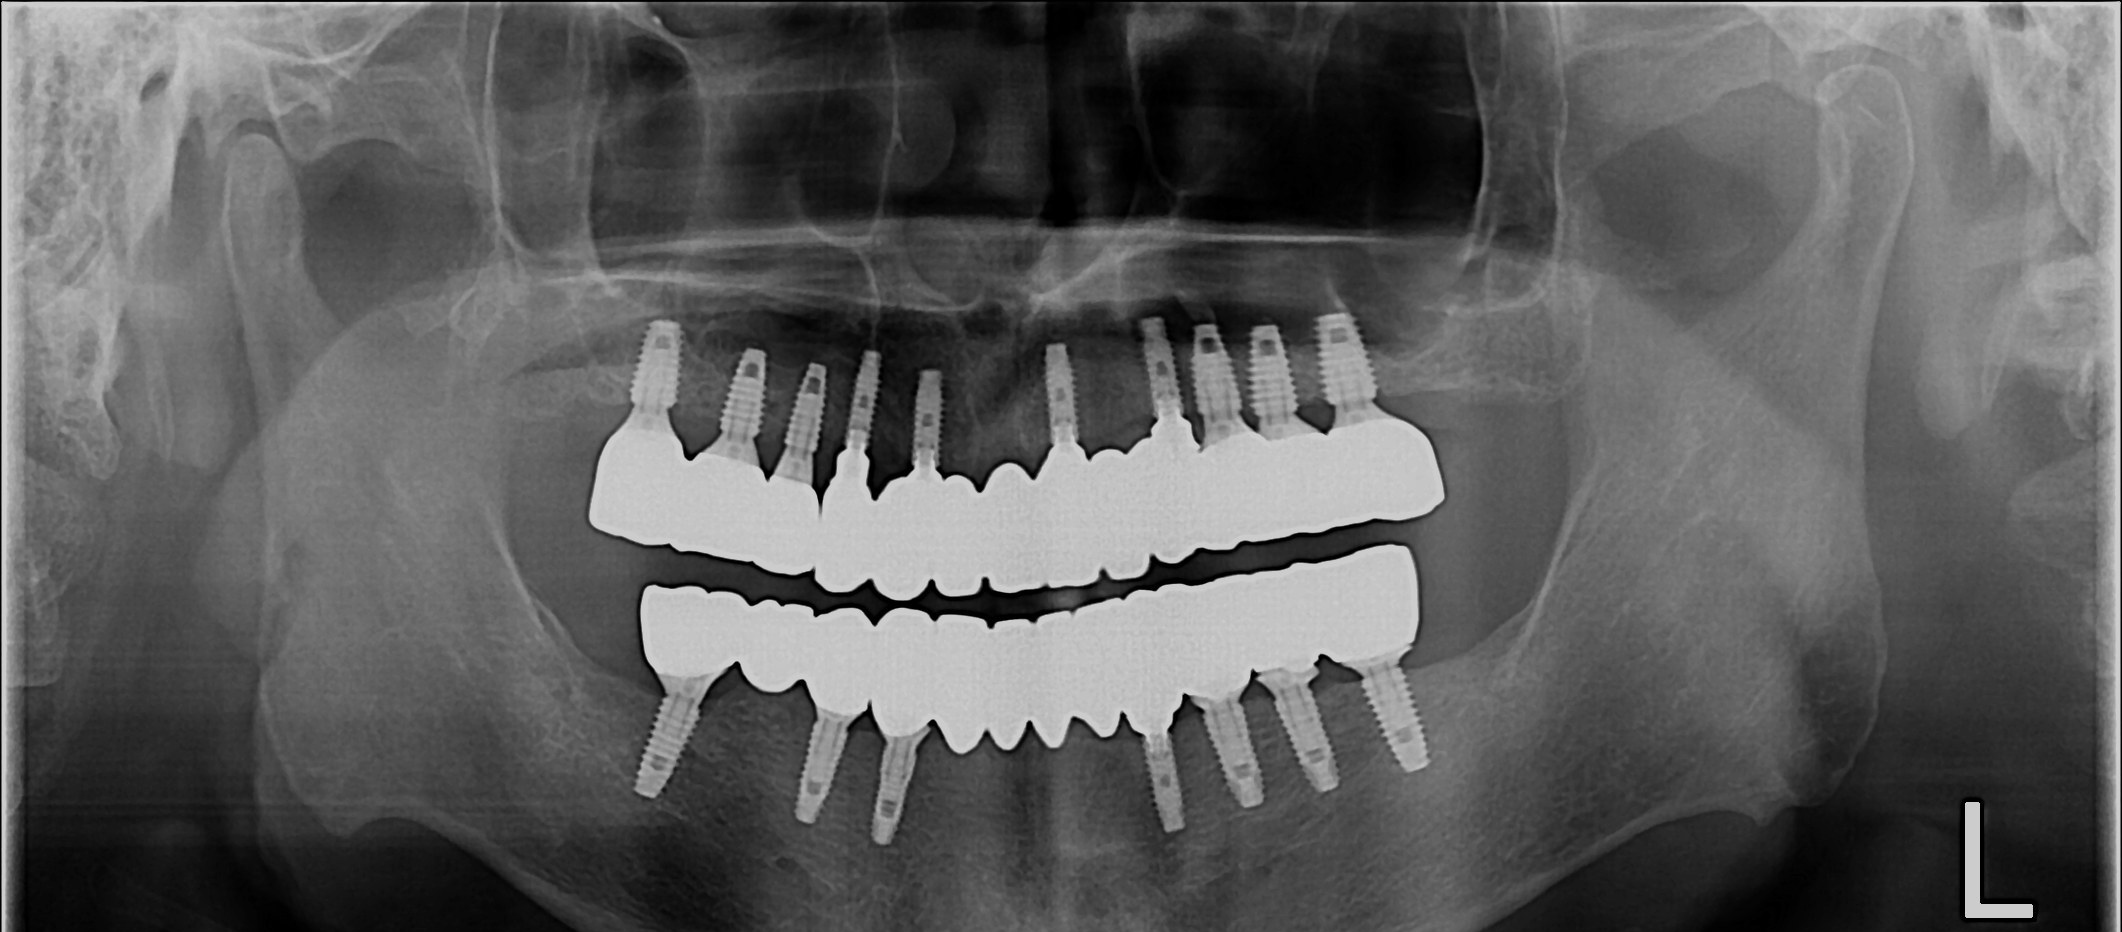

무치악 임플란트 회복

After

무치악 임플란트 회복 Full Mouth Rehabilitation

중간과정 ▼